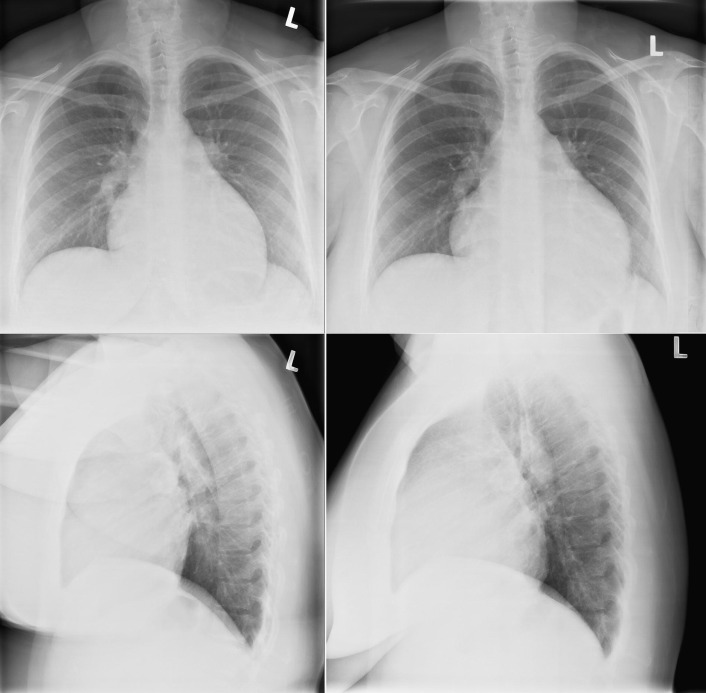

Constrictive Pericarditis

In constrictive pericarditis ( Graphic 16-1 ; Figs. 16-16 to 16-23 ) , the CPS is usually nonspecifically and mildly enlarged. Occasionally, the heart is normal or small in size. The left atrium is the most frequently enlarged chamber, because its enlargement is less restricted by pericardium. The right atrial contour on the frontal chest radiograph may be flattened. Calcification of the pericardium suggests past tuberculosis, but since tuberculosis has become uncommon at most centers, 90% of cases of constrictive pericarditis are currently noncalcified. Calcification, especially diaphragmatic, is not specific for constrictive physiology; it may be seen in the absence of cardiac compression. The apical surface is less frequently calcified than the interventricular and atrioventricular grooves. The apex seldom calcifies prominently in constrictive pericarditis; this finding suggests a calcified apical aneurysm rather that constrictive pericarditis.